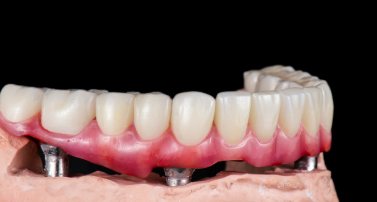

Os implantes dentários são uma solução

permanente para substituir dentes ausentes.

Eles consistem em pequenas peças de titânio

que são inseridas no osso da mandíbula,

funcionando como raízes artificiais. Após a

cicatrização, são inseridas coroas ou próteses,

proporcionando uma aparência natural e

funcionalidade total, restaurando a confiança e

o conforto do paciente ao falar e mastigar.

Implantes dentarios